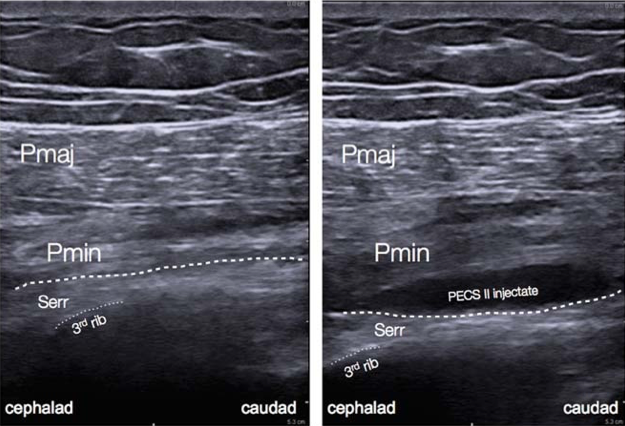

Figure 5: Ultrasound anatomy of pectoral nerve block II.[12

PECS blocks are becoming an increasingly popular technique for the provision of breast analgesia. PECS I blocks the medial and lateral pectoral nerves, which are situated in between the pectoralis minor and major muscles on the anterolateral chest. PECS II includes the PECS I block and an injection of local anesthetic into a plane more lateral on the chest wall and between the pectoralis minor and serratus anterior muscles, targeting the lateral cutaneous branches of the intercostal nerves, long thoracic nerve, and thoracodorsal nerve (Figure 5).[2] PECS II has been shown to be associated with lower postoperative pain scores and opioid consumption similar to PVB. However, the data is currently limited in terms of confirming which block is superior and they can both provide surgical anesthesia. The PECS block may be better tolerated by patients and easier to perform in the setting of decreased ancillary support or in an anesthetized patient. More extensive surgeries may require additional blocks to provide coverage for axillary procedures or medial breast analgesia.[6]